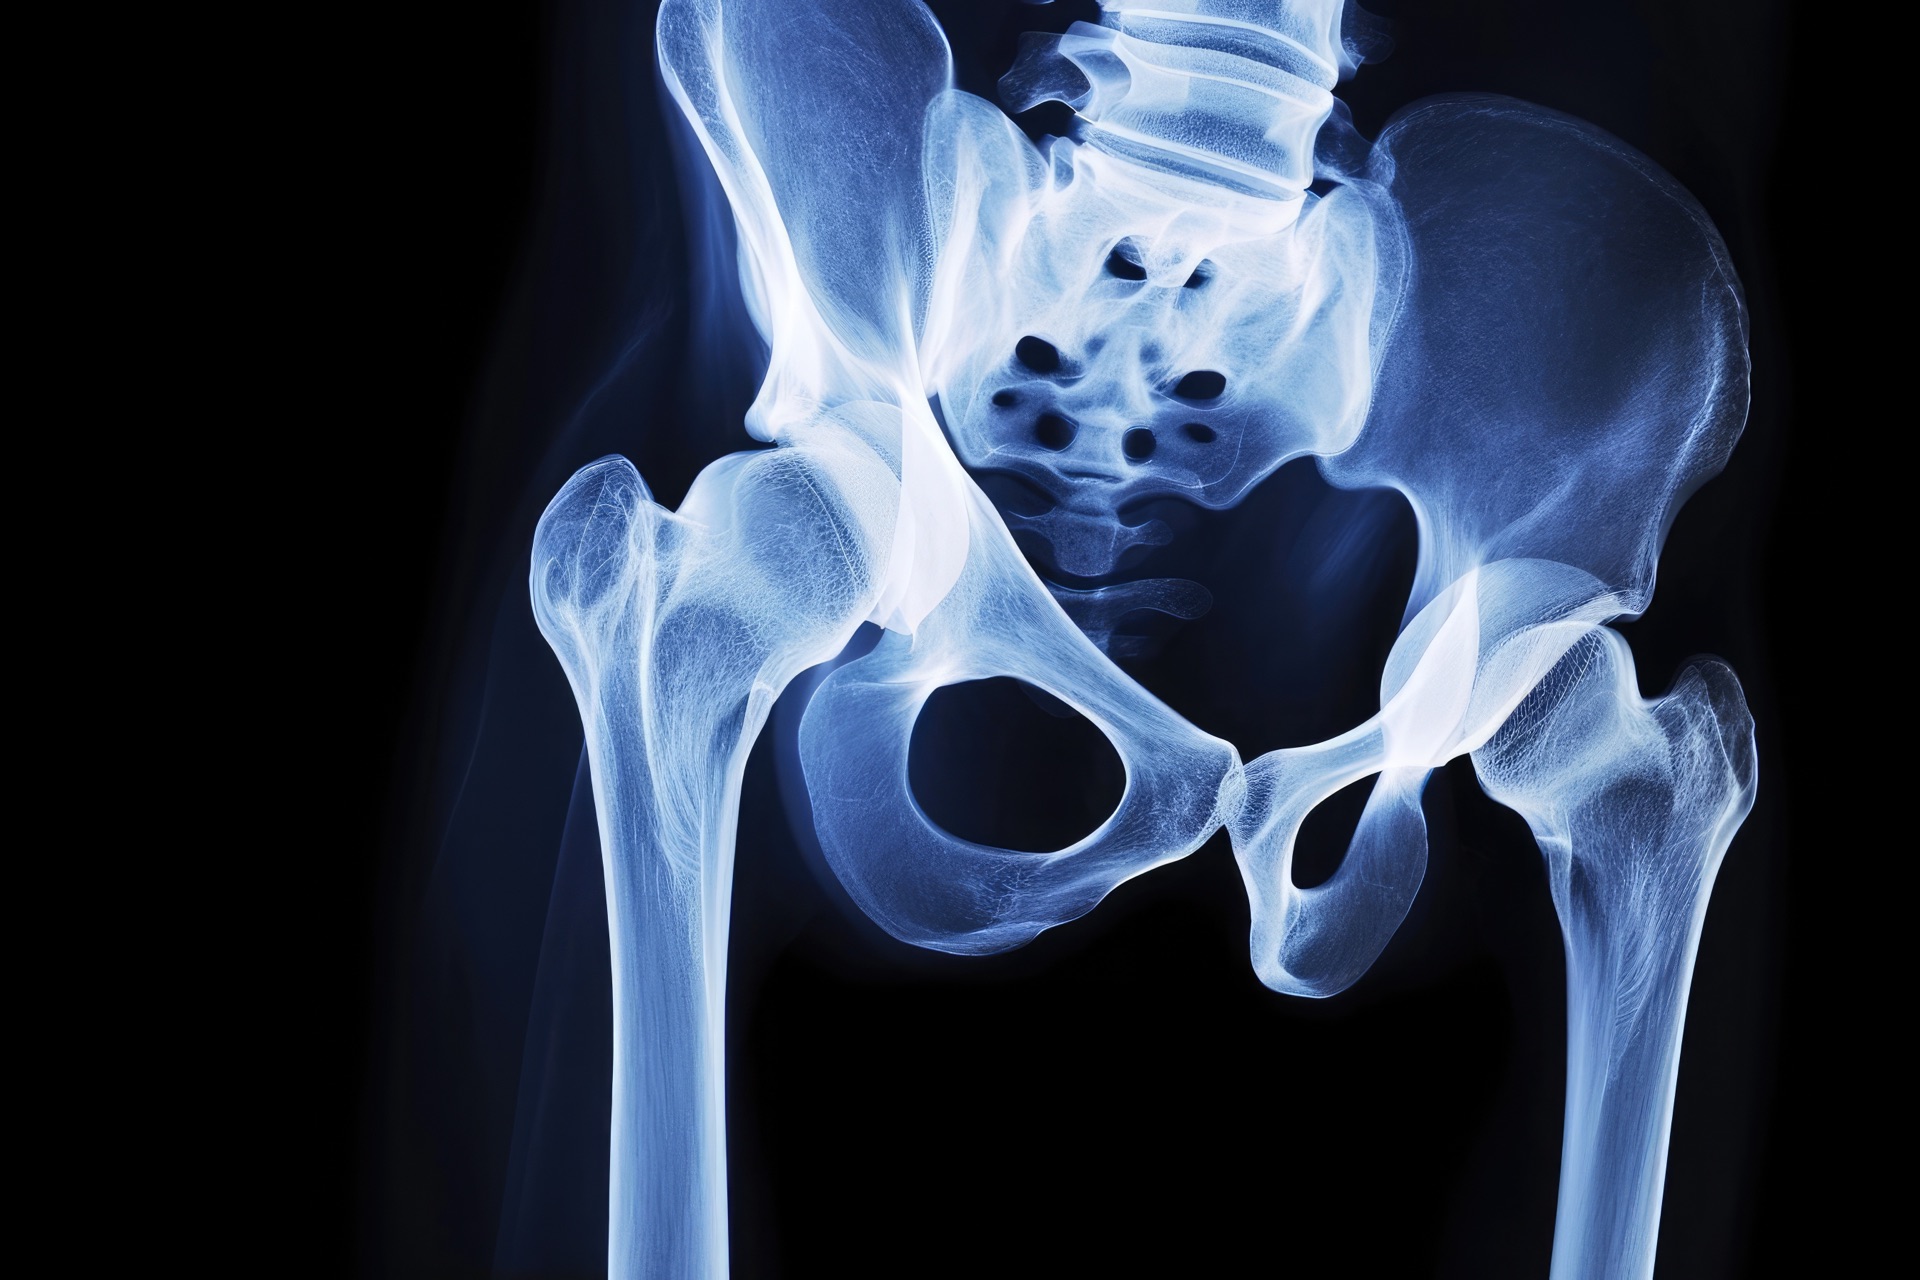

Advanced diagnostics for precise results

At our practice, we understand that an accurate and comprehensive diagnosis is the key to successful treatment. Our practice in Kreuztal-Ferndorf is equipped with modern diagnostic equipment that enables us to make quick and precise diagnoses.